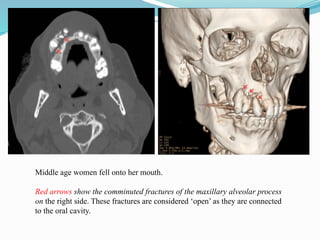

Isolated alveolar process fracture

 Fracture of any portion of the alveolar process

 Clinically evident by malalignment and displacement of teeth contained

within fractured segment

 Even on CT, fracture may be subtle and easily overlooked

 Further imaging may be needed when the diagnosis is made

X-ray of the teeth or a panoramic view (look for dental injuries)

Chest radiograph (look for aspirated teeth)

Middle age women fell onto her mouth.

Red arrows show the comminuted fractures of the maxillary alveolar process

on the right side. These fractures are considered ‘open’ as they are connected

to the oral cavity.